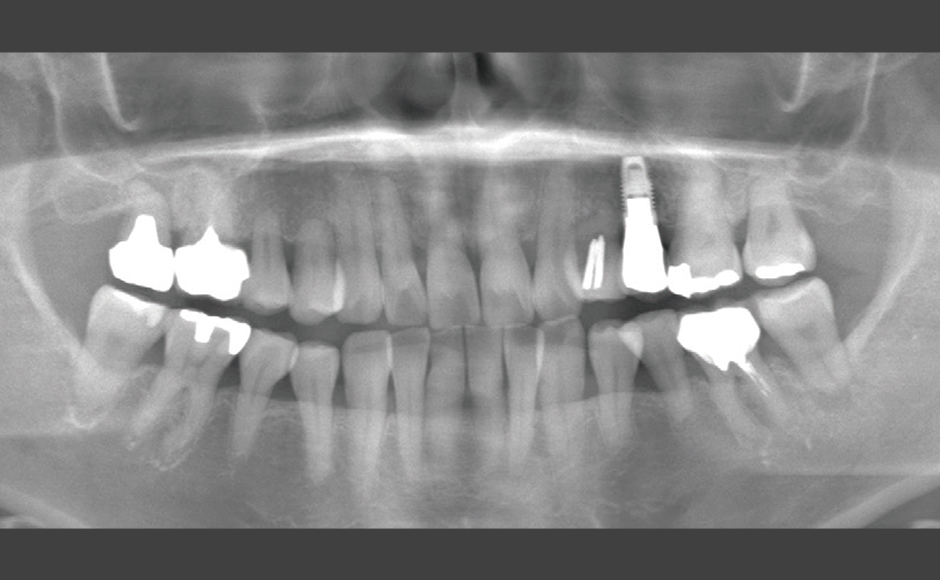

歯周病および根尖病巣により骨吸収、動揺が激しく、抜歯適応の歯牙に対し非外科的に歯周治療をNd:YAGレーザーを用いて行い、歯牙の保存を試みた症例